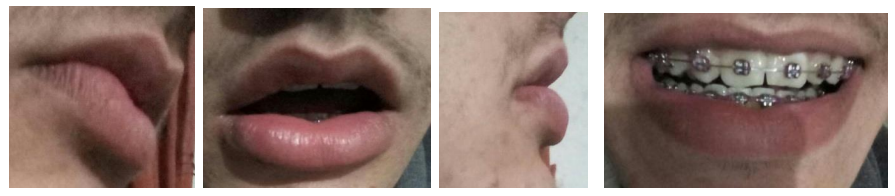

The aesthetic surgical outcomes were very satisfactory for both patient and surgeon. This is shown in frontal images after thirty days (Fig. 5) and in profile images six months after surgery (Fig. 6). Frontal and profile images three years after surgery (Fig. 7)

4. Treatment with the elliptical surgical excision technique, used in both lips in this specific case, provided very satisfactory psycho-emotional results for the patient in the short and long term (three years)